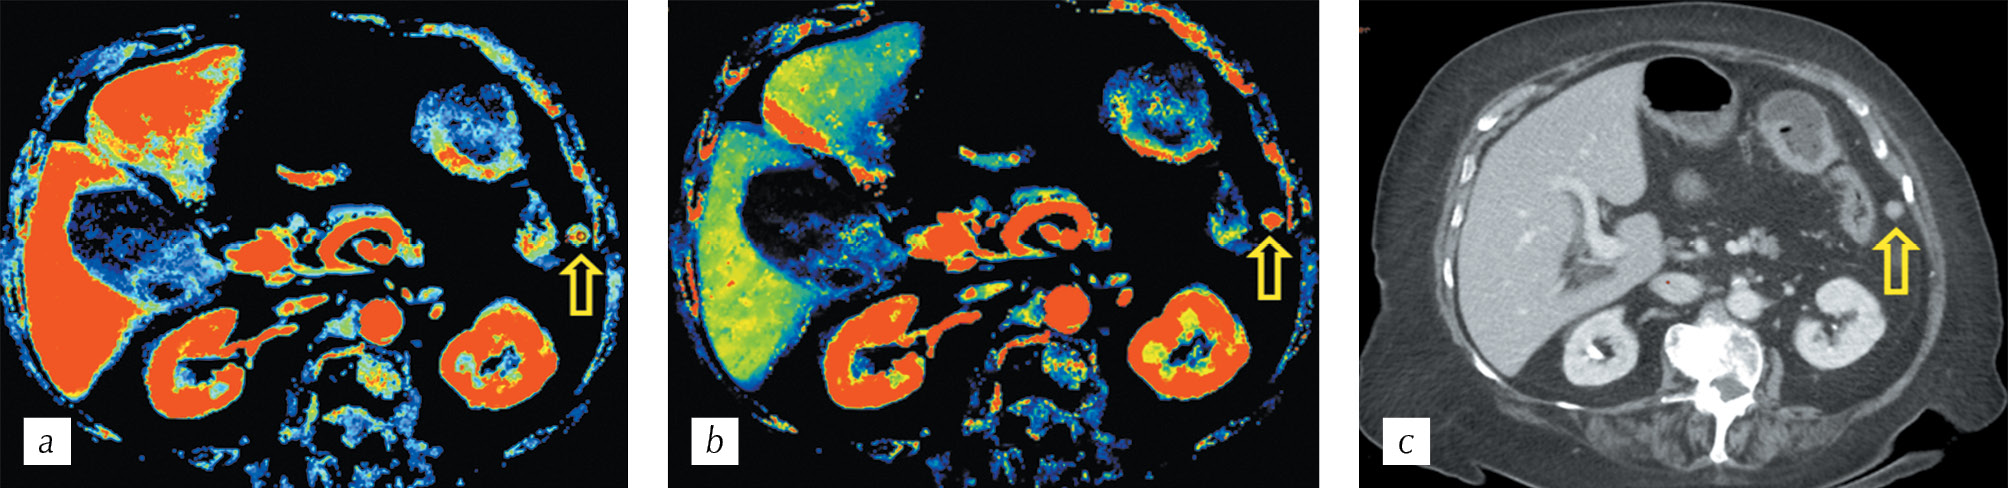

Similar analysis was also conducted in the secondary altered paracolic lymph node (Fig. 5).

Fig. 5. CT perfusion (a, b). Parametric maps: a — volume and b — blood flow showing pathological increased blood flow in the paracolic lymph node (arrows); c — HCT. Multiplanar reconstruction in the axial plane in the portal phase of scanning

Рис. 5. Перфузионная компьютерная томография (a, b). Цветные параметрические карты: а — объема и b — скорости кровотока, демонстрирующие патологический повышенный кровоток в параколическом лимфатическом узле (стрелки); c — спиральная компьютерная томография. Мультипланарная реконструкция в аксиальной плоскости в портальную фазу сканирования